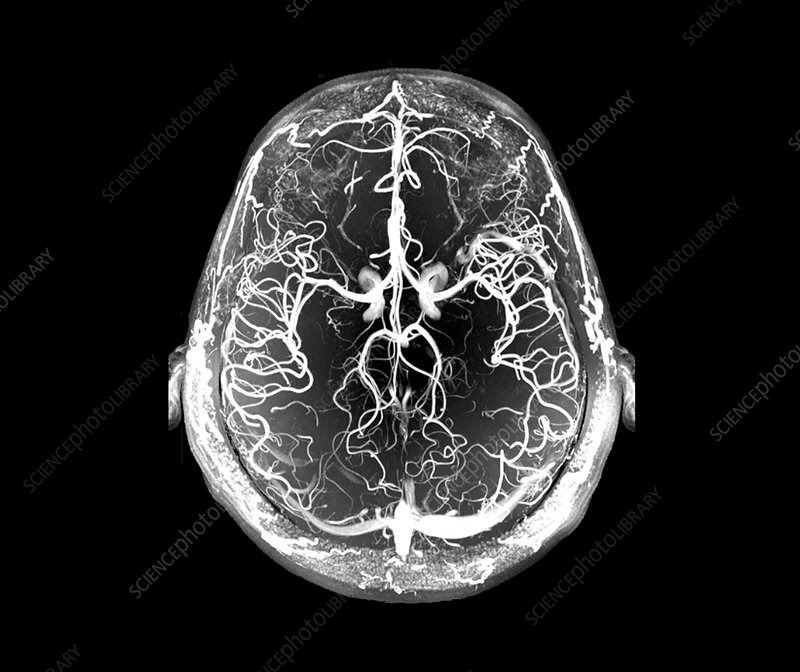

There is no way that Phineas Gage could have known that what had happened to him would revolutionize the field of neurology, but it most certainly did. When I worked as an interventional radiology nurse, patients would be sent to us after having had a stroke, and through a groin puncture, the neurosurgeon would quickly snake wires all the way through the vasculature up to the brain, then would light up the brain’s vascular structure of each hemisphere with contrast to see where the blood embolus was, and suck it out. In a day or so, patients would regain most of their function.

https://www.sciencephoto.com/media/1193526/view/blood-vessels-of-the-brain-mri-angiography

That was always amazing for me to see, and it shows how far we’ve really come with understanding the human body and the brain, even if there is still a lot we don’t understand.